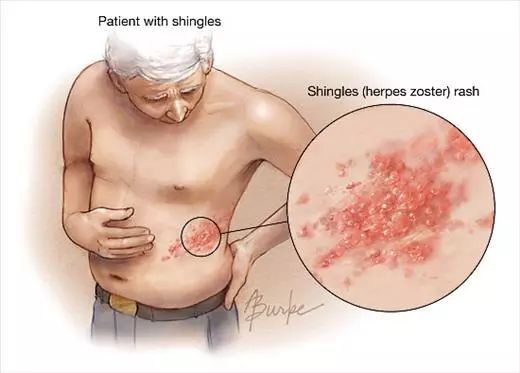

只不过,当它复发时就不再叫做水痘,而是被称为带状疱疹。

据《2016 带状疱疹后神经痛诊疗中国专家共识》估计:60岁以上带状疱疹患者PHN发生率为65%,70岁以上带状疱疹患者PHN发生率为75%。当这些VZV病毒重出江湖时,它们会沿着我们的感觉神经轴突到达所支配的皮肤细胞,继而在细胞内增值引起疱疹。这样生成的疱疹沿一侧周围神经作群集带状分布。这也正是它叫做带状疱疹的原因。

在传统医学上,带状疱疹常被称为金蛇、金龙缠腰,又或者缠腰火丹等。因为它长出的疹子常出现在腰部及后腰部,或是沿着肋间神经分布。那又红又热的疹子可谓是绕着身体走了大半圈,如同一条龙缠在身上一样。

与当初水痘痒得令人抓狂不同,带状疱疹是从神经发出的剧痛,分分钟让人痛不欲生。当然,这疼痛也是沿着那根受累的神经所支配的区域分布的。一些人带状疱疹只发在肋间神经的背后那段,就只有背后痛;另一些人发在面神经上,就半边脸痛。

带状疱疹局部图